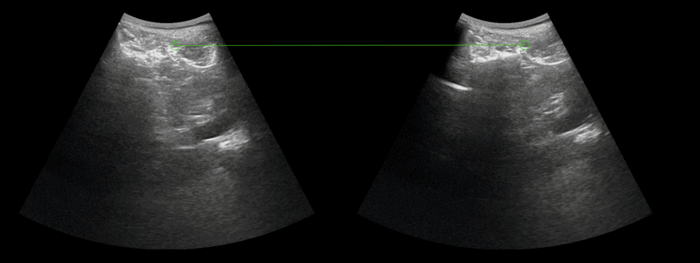

Example result: Correspondences computed between different US sweeps, PLUS kidney data

Preliminary Results: Features correspondences, Kidney Ultrasound Sweeps